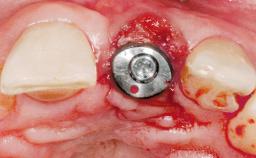

Immediate Flapless Placement of an Implant in a Maxillary Right Lateral Incisor Site

This 43-year-old male patient, a non-smoker, came to our practice because of a fracture of tooth 12 caused by a bicycle accident. Due to the combined para- and infrabony crown and root fracture, tooth extraction, and subsequent implant placement were suggested to the patient as the therapy of choice. The patient had high esthetic expectations with regard to the treatment outcome and asked for an immediate fixed provisional restoration. His individual esthetic risk profile summed up to a medium esthetic risk.

Placement Protocol Immediate implant placement

Loading Protocol Immediate

Retention Screw-retained Screw-retained

Provisional Implant-Supported Prosthesis Prosthodontic margin > 3 mm apical to mucosal margin Prosthodontic margin > 3 mm apical to mucosal margin